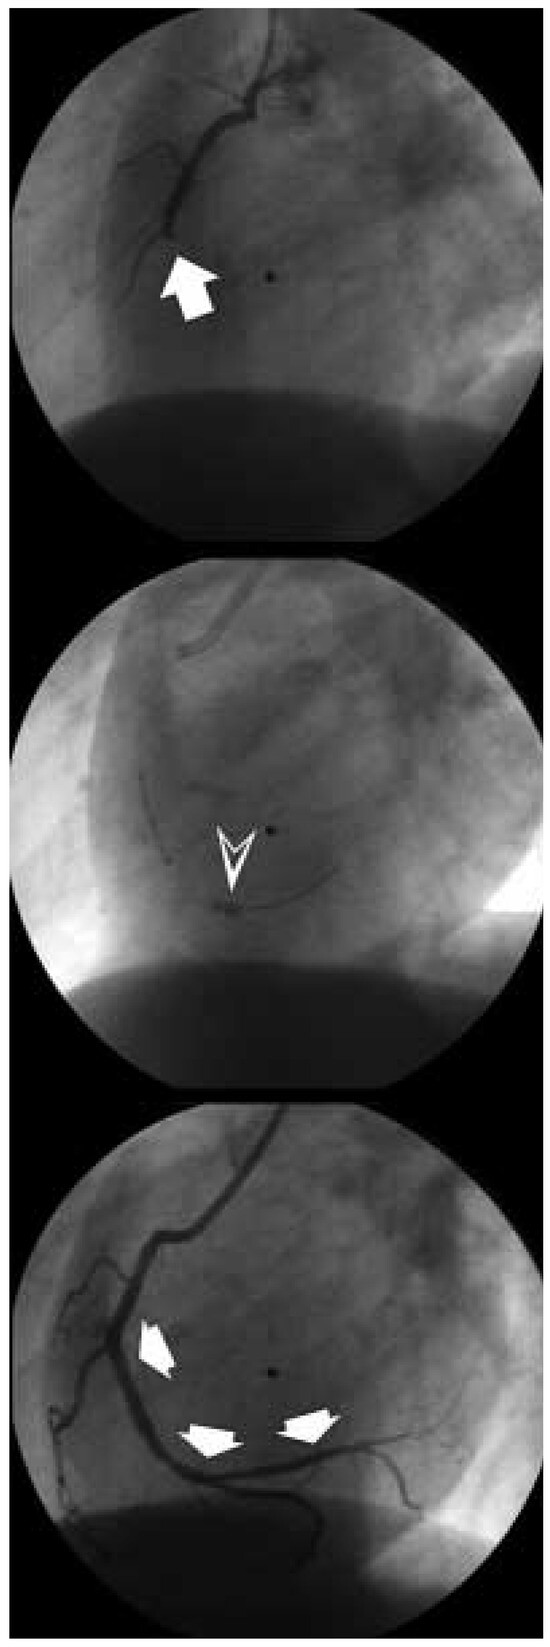

Dreidimensionale Angiosonographie

by Michel Zuber

Viele Gefässsysteme lassen... Full article

Show Figures

Figure 1